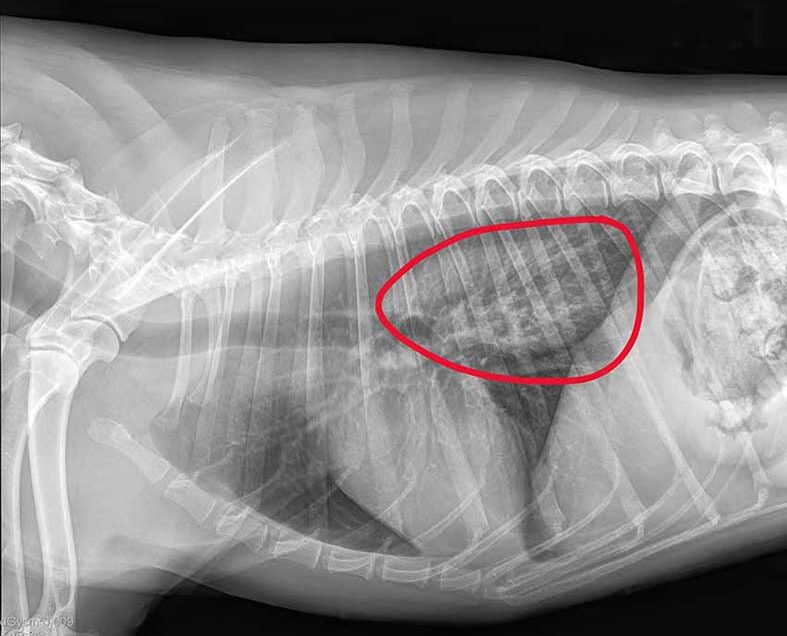

Aufgrund der Vorgeschichte entschied sich Tierärztin Sabine Gigl nach Absprache mit den Besitzern für eine Röntgenuntersuchung, um nach Hinweisen für einen möglicherweise steckengebliebenen Fremdkörper zu suchen. Die Aufnahmen zeigten eine auffällige, helle, verwaschene Stelle hinter dem Herzen. „Unser Verdacht erhärtete sich, dass das Rinderohr in der Speiseröhre steckt“, so Gigl.

Eine auffällige, helle, verwaschene Stelle hinter dem Herzen bestätigt den Verdacht, dass ein Fremdkörper in der Speiseröhre steckt.